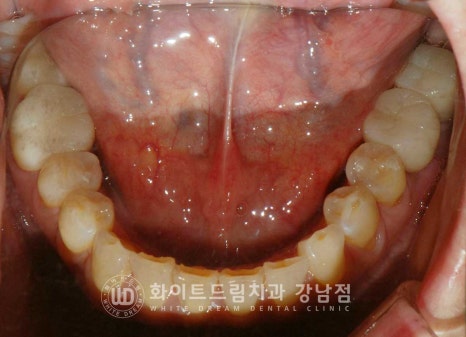

환자분의 치료 전/후 구내 사진입니다.

동일 인물이며 동일 환경에서 촬영되었습니다.

23.03.07 - 23.09.26

식립된 임플란트들이 상실된 치아의 기능을 정상적으로 이행함을 확인하며

치료를 마무리하게 되었습니다.